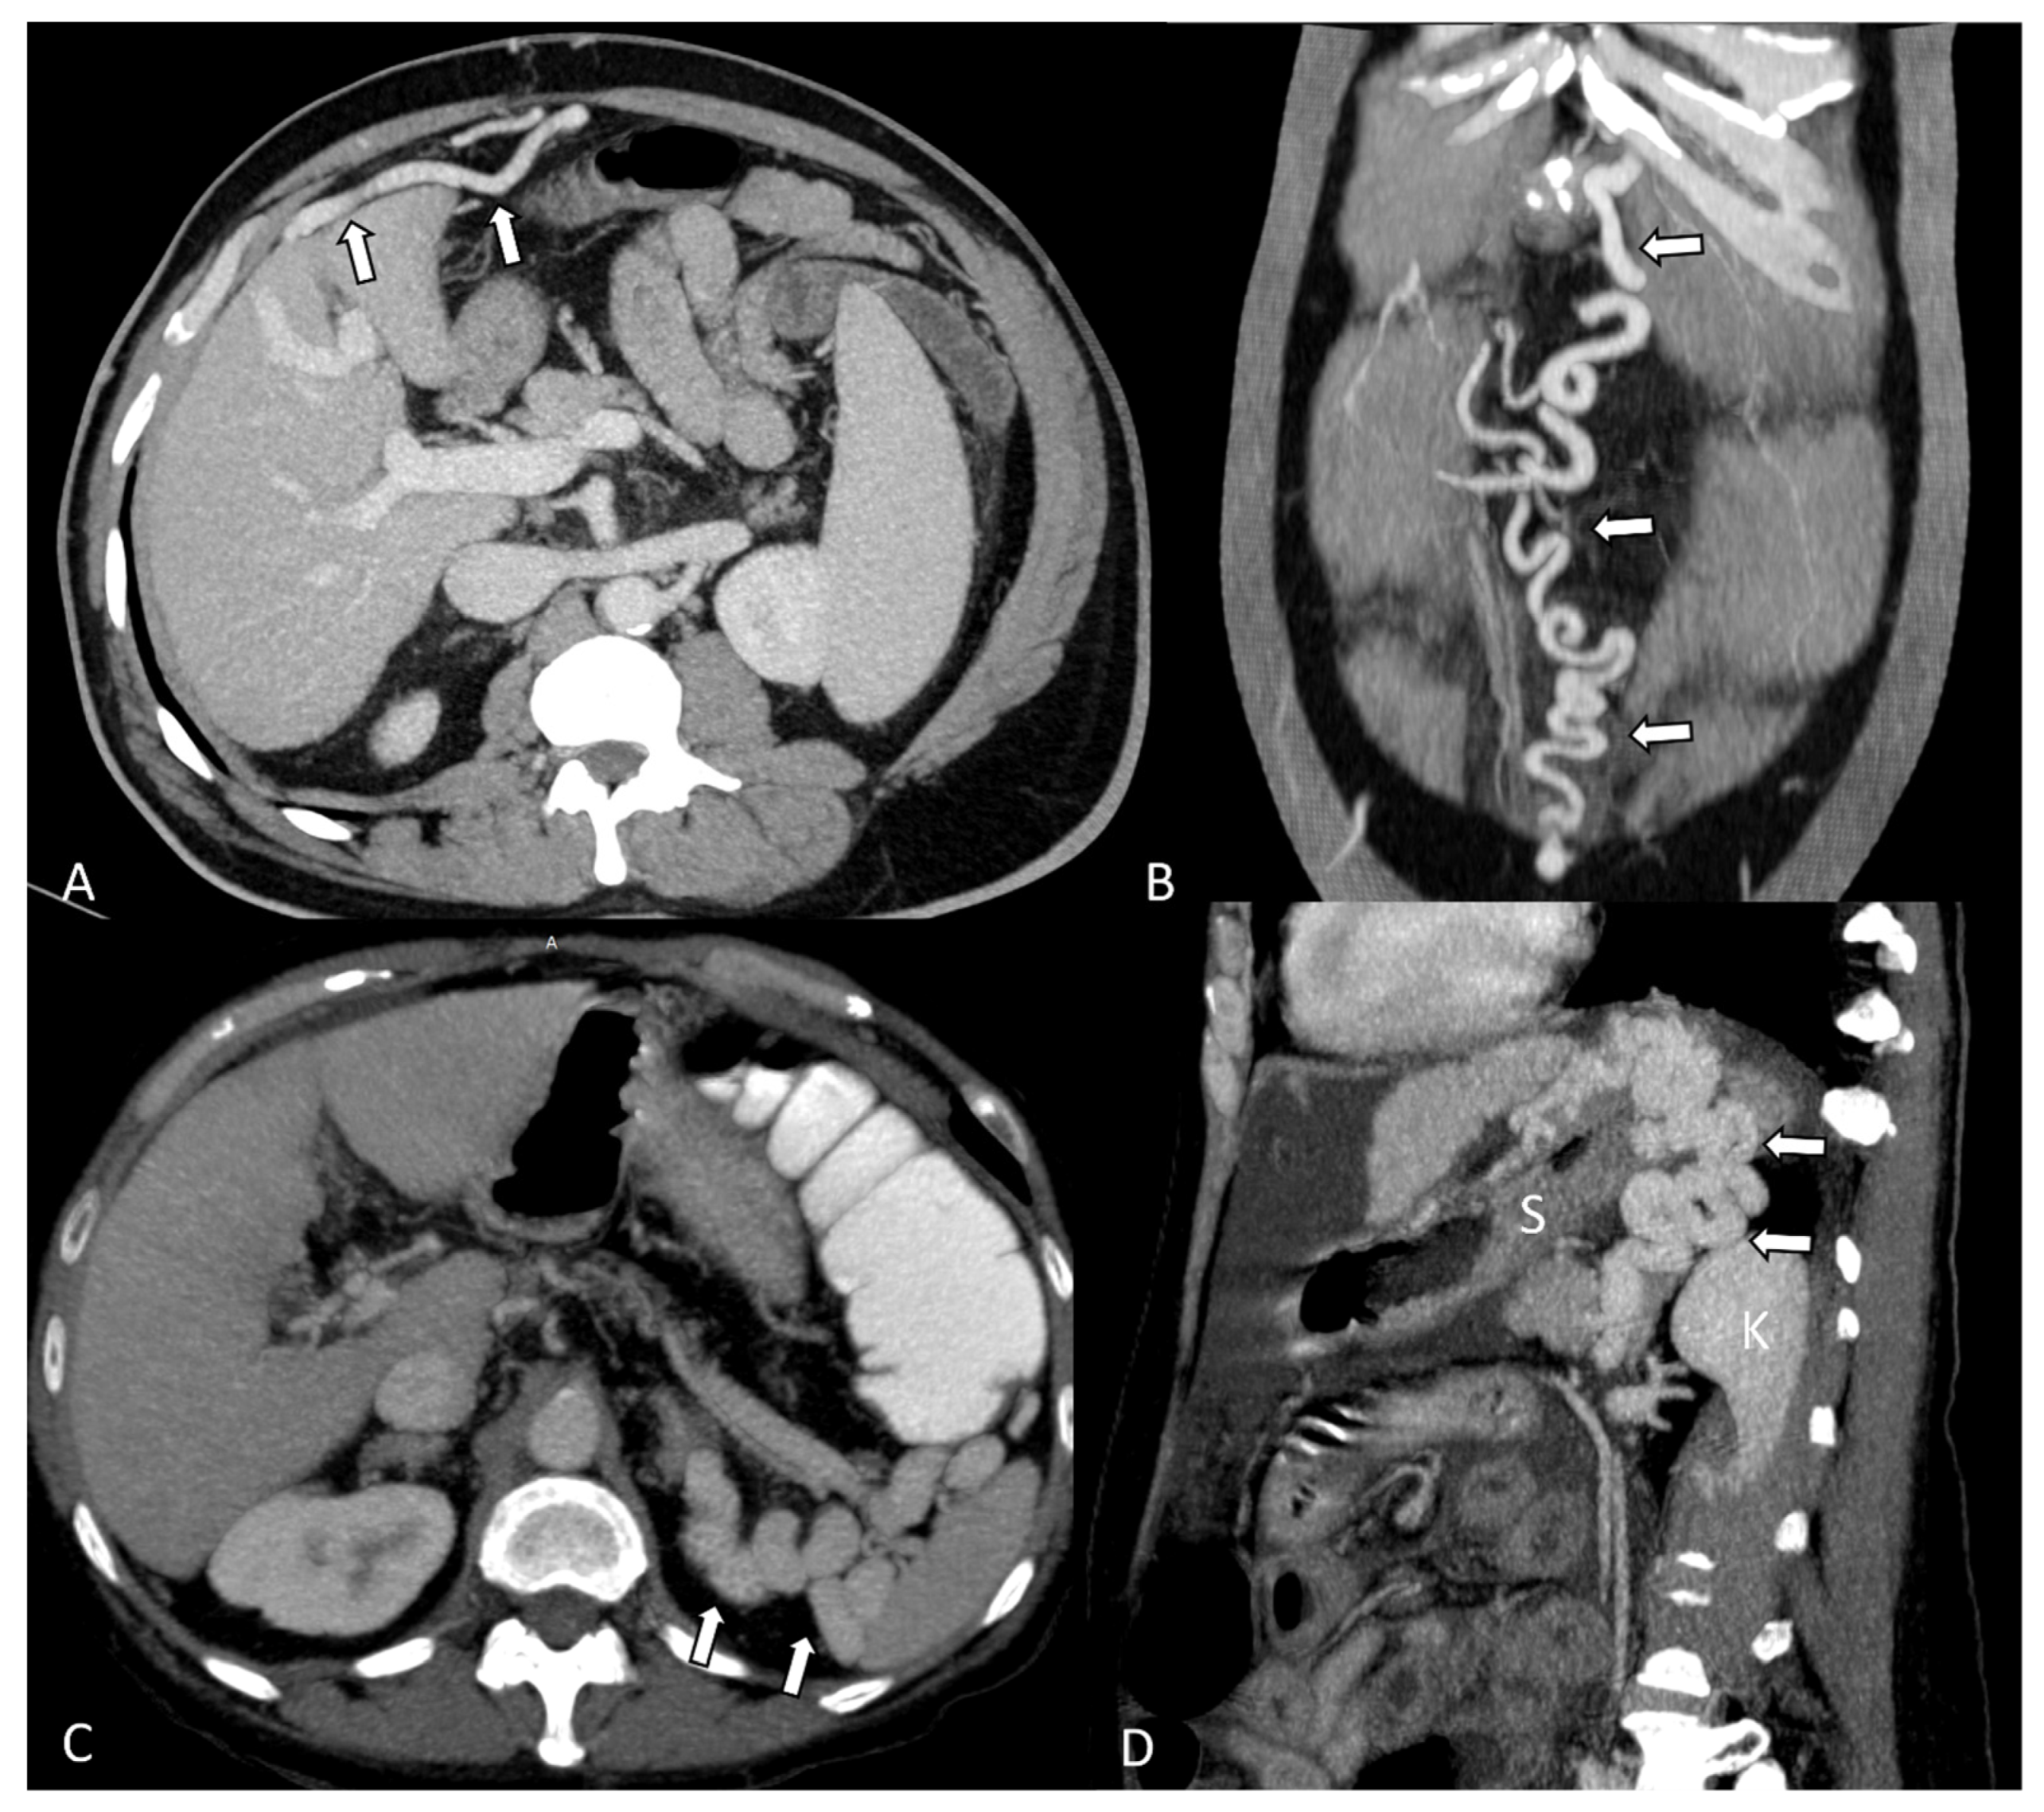

- Henseler, K.P.; Pozniak, M.A.; Lee, F.T.; Winter, T.C. Three-dimensional CT angiography of spontaneous portosystemic shunts. Radiographics 2001, 21, 691–704. [Google Scholar] [CrossRef]

- Yi, F.; Guo, X.; Zeng, Q.L.; Yang, B.; He, Y.; Yuan, S.; Arora, A.; Qi, X. Computed Tomography Images of Spontaneous Portosystemic Shunt in Liver Cirrhosis. Can. J. Gastroenterol. Hepatol. 2022, 2022, 3231144. [Google Scholar] [CrossRef] [PubMed]